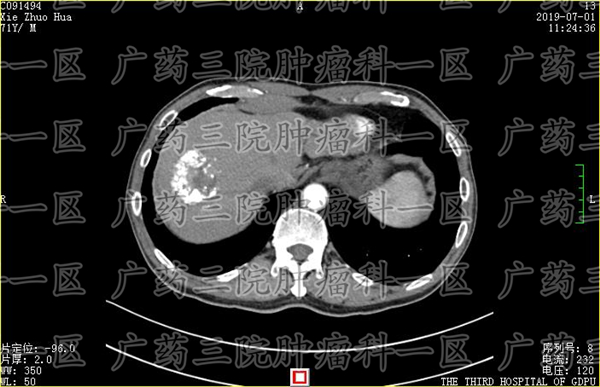

肝内胆管癌的恶性程度比较高,其治疗方案也更依赖因人而异。广药三院肿瘤科一区医生指出,不同的肿瘤患者,病理类型不同,病情发展程度不同,治疗的方案自然也各不相同。对肝内胆管癌,有的患者适合手术切除,有的患者不能。

不同患者身体素质b不同,耐受程度也不同,因此,合适的治疗方案也不同。彭齐荣主任团队医生坚持为每位患者进行多学科会诊,多位医生为一名患者进行会诊讨论。通过仔细了解患者的病情和检查资料后,制定合适的微创综合治疗方案。

肝内胆管癌 患者可以选择传统的开刀手术治疗,也可以选择微创治疗。考虑到很多肝内胆管癌患者确诊时恶性程度很高,甚至有的已经出现骨转移等转移病灶,已经不适合进行传统开刀治疗。广药三院肿瘤科一区医生可以为i患者提供微创综合治疗方案。

而患者如果选择微创治疗,广药三院肿瘤科一区医生的建议是,患者可以考虑微创与免疫结合的综合疗法。如果病人年纪偏大,或者已经有转移,可能无法耐受手术,那么这时建议患者选择微创综合治疗来保守治疗。医生会先为患者会诊,拿到病理学的依据,根据结果,可以给予病人进行微创治疗。